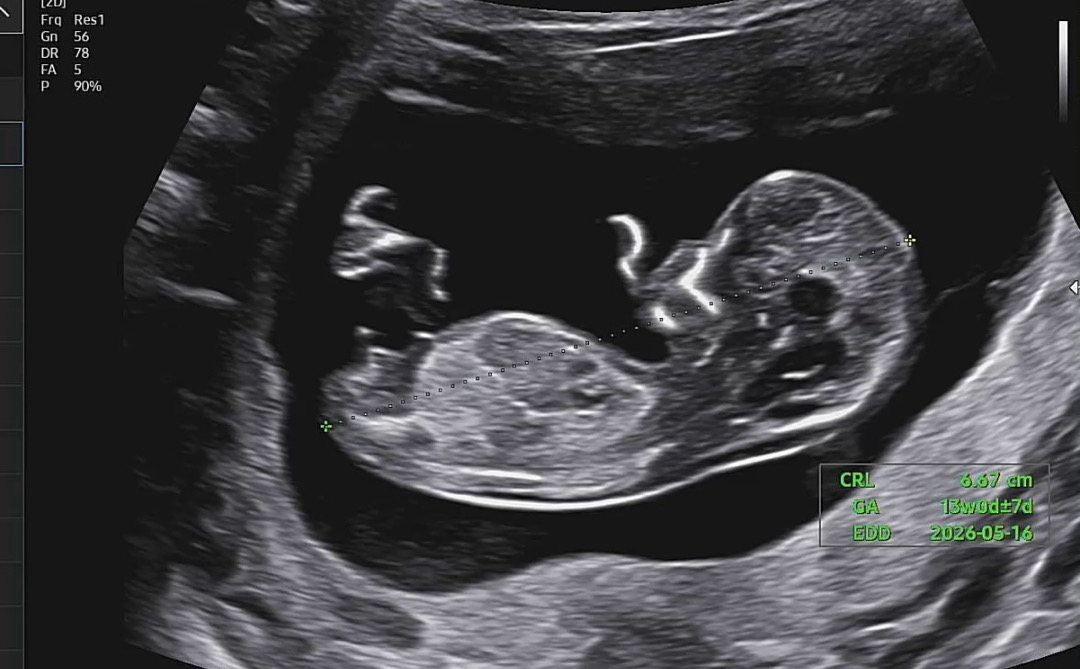

오늘 기형아 1차 검사 했는데 각도법 봐주세용😇🫶🏻

여아일까요? 남아일까용??? ㅎㅎㅎ